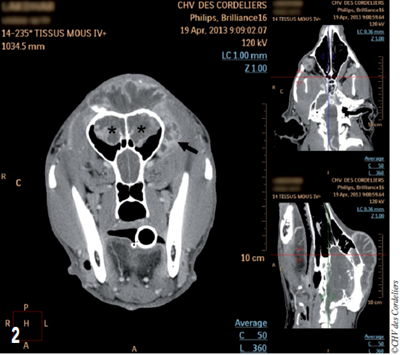

- Rostralement, la masse recouvre les sinus frontaux dorsalement et les envahit (photo 2).

- Caudalement, le tissu hyperdense après l’injection de produit de contraste s’étend jusqu’au milieu de la crête occipitale.

- Latéralement, la masse déborde de façon plus importante du côté gauche avec un envahissement du processus zygomatique de l’os frontal et s’étend 1 cm en arrière de l’œil (photo 3).

Photo 2 : Aspect tomodensitométrique de la masse : notez l’envahissement des sinus frontaux (étoiles) et la latéralisation à gauche (flèche).

Aucune compression du cerveau n’est visible au scanner.

Photo 3 : Aspect tomodensitométrique de la masse en vue sagittale : la masse s’étend très caudalement (flèche).